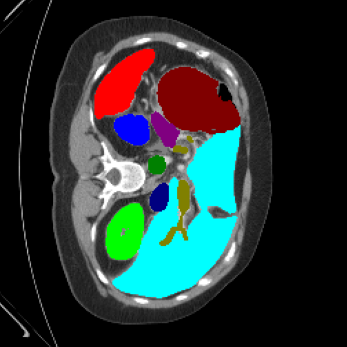

We begin by qualitatively inspecting our model. Figure 3 compares the output of LoGoNet to the best performing baseline model in BTCV dataset, i.e., DiNTS Search (more qualitative comparisons can be found in appendix section 11). We see that our model particularly excels in segmenting organ boundaries. This can be attributed to our effective strategy for extracting local-range dependencies, which plays a crucial role in extracting details from input data. Our model’s adeptness in capturing long-range dependencies allows it to grasp contextual information that extends over significant distances within the data. Simultaneously, its proficiency in handling short-range dependencies ensures precision in capturing localized patterns.